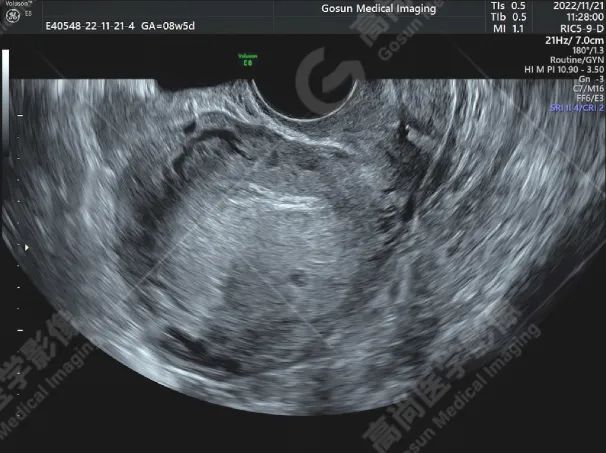

前位子宫,包膜光滑完整,形态饱满,实质回声不均匀增粗,内膜前移、清晰,厚约 15 mm;左侧宫角可见一向外突起的混合回声团块,大小约 34 mm×27 mm,边界欠清,形态尚规则,内部可见多处大小不等的无回声区,内侧与宫腔不相通,外侧肌层不完整,局部仅可见浆膜层,CDFI 显示其内可见丰富血流信号,PW 显示内部 Vp = 45 cm/s,RI = 0.23。

左侧宫角旁混合性包块 (考虑左输卵管间质部妊娠);子宫腺肌病;双侧卵巢未见明显异常。